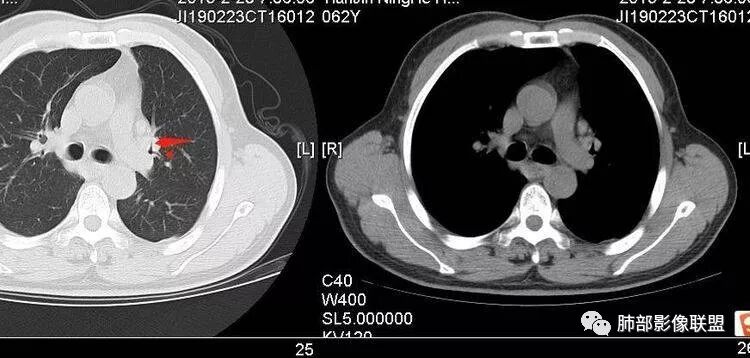

王秀仙:左肺上叶肿块,边缘平直收缩,周围可见长索条,轻度强化,密度不均可见低密度坏死,考虑结核。鉴别腺癌。Yiren  Sishui(厶水伊人):晨读:左肺上叶肿块,近胸膜侧光滑,提示符合淋巴回流病变,周围条索,符合肉芽肿性病变,环形强化,中心坏死,考虑结核可能luys:左肺上叶病变,沿支气管分布,边缘平直收缩,周围见长索条,轻度强化,伴边界可见低密度坏死灶。考虑特殊感染。灶内支气管中断,临床以咯血就诊,鉴别肿瘤。博麟:左上胸廓稍缩小,长条索病灶,冠状位似见支气管截断,坏死边界似乎欠清,猜个纤维条索基础上合并瘢痕癌红日东升:晨读:左上叶结块,前缘有粗大索条向前延伸,邻近前联合线明显左移,提示收缩明显。结块边缘平直、收缩;增强结块及索条明显强化,内血管走行自然,坏死灶周围似见三层结构;考虑炎性病变。wonderful:肿块实性边缘光滑  考虑良性病变 合并咯血 。结核或曲霉玫:左肺上叶不规则形软组织密度肿块影,边界清晰,期内密度不均匀,可见坏死,病灶向前呈条索状延伸,矢状位病灶形态欠规整,似有血管中断,考虑恶性病变可能,待除外结核?张帅:左肺上叶病变,病变周围平直,长毛刺,病灶内可见低密度区及支气管征,矢状位提示前段阻塞,病灶内气管不规则扩张,病灶周围有卫星灶,考虑良性病变:结核?我心飞翔:病灶边缘平直,中央可见坏死,周围磨玻璃边界欠清,考虑炎性病变张延军:左肺上叶尖后段肿块,边缘以平直为主,局部膨隆,内见片状坏死区,边界欠清,相应尖后段支气管闭塞,考虑占位并不张,腺癌?建议抗炎治疗后复查丽:左肺上叶病变,边缘平直,并可见长索条,增强后密度不均,可见坏死,首先考虑结核,但重建后支气管走形欠连续,似有截断,恶性待排毛勤香:左肺上叶病灶,边缘平直为主,周围索片影,增强强化不均匀,内有坏死,重建支气管走行欠规则,似有截断,老年男性,需排除恶性(鳞癌?)并阻塞性肺炎可能王萍:左肺上叶团片,大部分边缘平直、凹陷,周围见少许条片模糊影,增强内见坏死区,余区域较均质,其内支气管部分通畅,部分变窄。咯血病史,无发热,考虑肉芽肿性炎可能性大,结核或放线菌等,肿瘤待排THINKER:左上叶,占位,围绕尖后段支气管,U型凹丶平直,长索条,有轻强化及低密度,考虑良性的,首选OP,老年不发热丶咯血,鉴鳞癌、TB飞鹰行动:左肺病灶,有明显的收缩表现,增强后病灶内部可见低密度无强化区,病灶内支气管轻度扩张呈串珠状改变,支持炎性病变,结核可能性大。杨泽锋:支持炎性病变伴小脓腔形成,但不支持结核,因为病灶内可以可见血管影THINKER:问一下各位老师:这个给的强化,是肺动末期丶主动脉未期`延迟期?大雄:老年男性,左肺上叶前段条片状实变影伴周围长条索,境界清晰,边缘部分锐利光滑、部分毛糙,增强可见中央局部坏死,周围无强化区轻中度均匀强化,无钙化,无明显卫星灶,无胸膜明显牵拉凹陷。病灶整体收缩力有,张力不明显,肿瘤概率小。临床无明显急性感染症状,倾向于慢性增生性炎症,累及段支气管,引起了咯血。结核多见,但慢性结核肉芽肿一般强化没这么明显。OP不除外。老年男性如果有长期吸烟史,鳞癌不能完全排除,鳞癌的坏死强化都符合,鳞癌收缩力也不强,形态更是变化无常左手:老年男性,咯血,左肺上叶长条样结节,边缘见牵拉影,支气管堵塞,病灶内见坏死,坏死边缘偏清,考虑鳞癌,鉴别结核宇宙星空:支持恶性。鳞癌可能性大。支气管截断及空泡征

Shelia:考虑机化性肺炎伴小脓肿形成?炎性肌纤维母细胞瘤?鉴别癌食客:左肺上叶病灶,边缘平直,周围条片影,增强内见坏死区,内支气管部分通畅,咯血病史,无发热,考虑结核,肿瘤不除外。管洪林:左肺上叶尖后段病变,整体边缘平直,部分稍收缩,临近长索条影,胸膜缘可见轻度牵拉,增强后整体强化明显,其内可见低密度类圆形坏死区,边界清,首先考虑op并小脓肿形成,但部分层面显示小支气管受阻,是否层面原因?管洪林:若是支气管阻塞,鳞癌作为鉴别雪上一枝蒿(陈显静):他这个动脉期是不是不是很明显啊,觉得跟静脉期差不多,强化值也不好分辨?徐超:左肺上叶实变,边缘平直,周围无磨玻璃及卫星灶,病灶内坏死,强化后边界清楚,无壁结节,余病灶轻中度均匀强化(对比肌肉),增强后血管显影清楚自然,未见破坏边缘毛糙,血管旁条形无强化区(粘液?)整体符合炎性特点,炎性假瘤或op可能,伴小脓肿;结核放后面待排(结核病灶内血管完好,边缘清楚,且强化近中度,不是很合理,肉芽肿到也可以)。红日东升:平扫和强化窗宽窗位不一样良孑:左上实变,有平直及长毛刺,其内支气管牵拉性扩张,提示收缩力较强,无卫星灶,强化不支持TB,均匀强化,无分叶不支持鳞癌,影像上提示慢性进程,考虑OP并脓肿,鉴别炎肌母。

宇宙星空:看远端的话是狭窄了吧,但是近端明显是截断啊,远端的是肺泡腔?

南边:没有堵塞考虑啥?

宇宙星空:炎性病变

宇宙星空:病灶长片状,部分边缘平直光滑,

南边:还是支持炎性吧

炎性假瘤